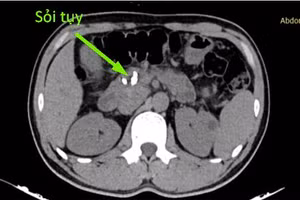

GD&TĐ - Bệnh nhân nhập viện tại Trung tâm Y tế khu vực Cẩm Khê trong tình trạng đau bụng dữ dội vùng thượng vị.